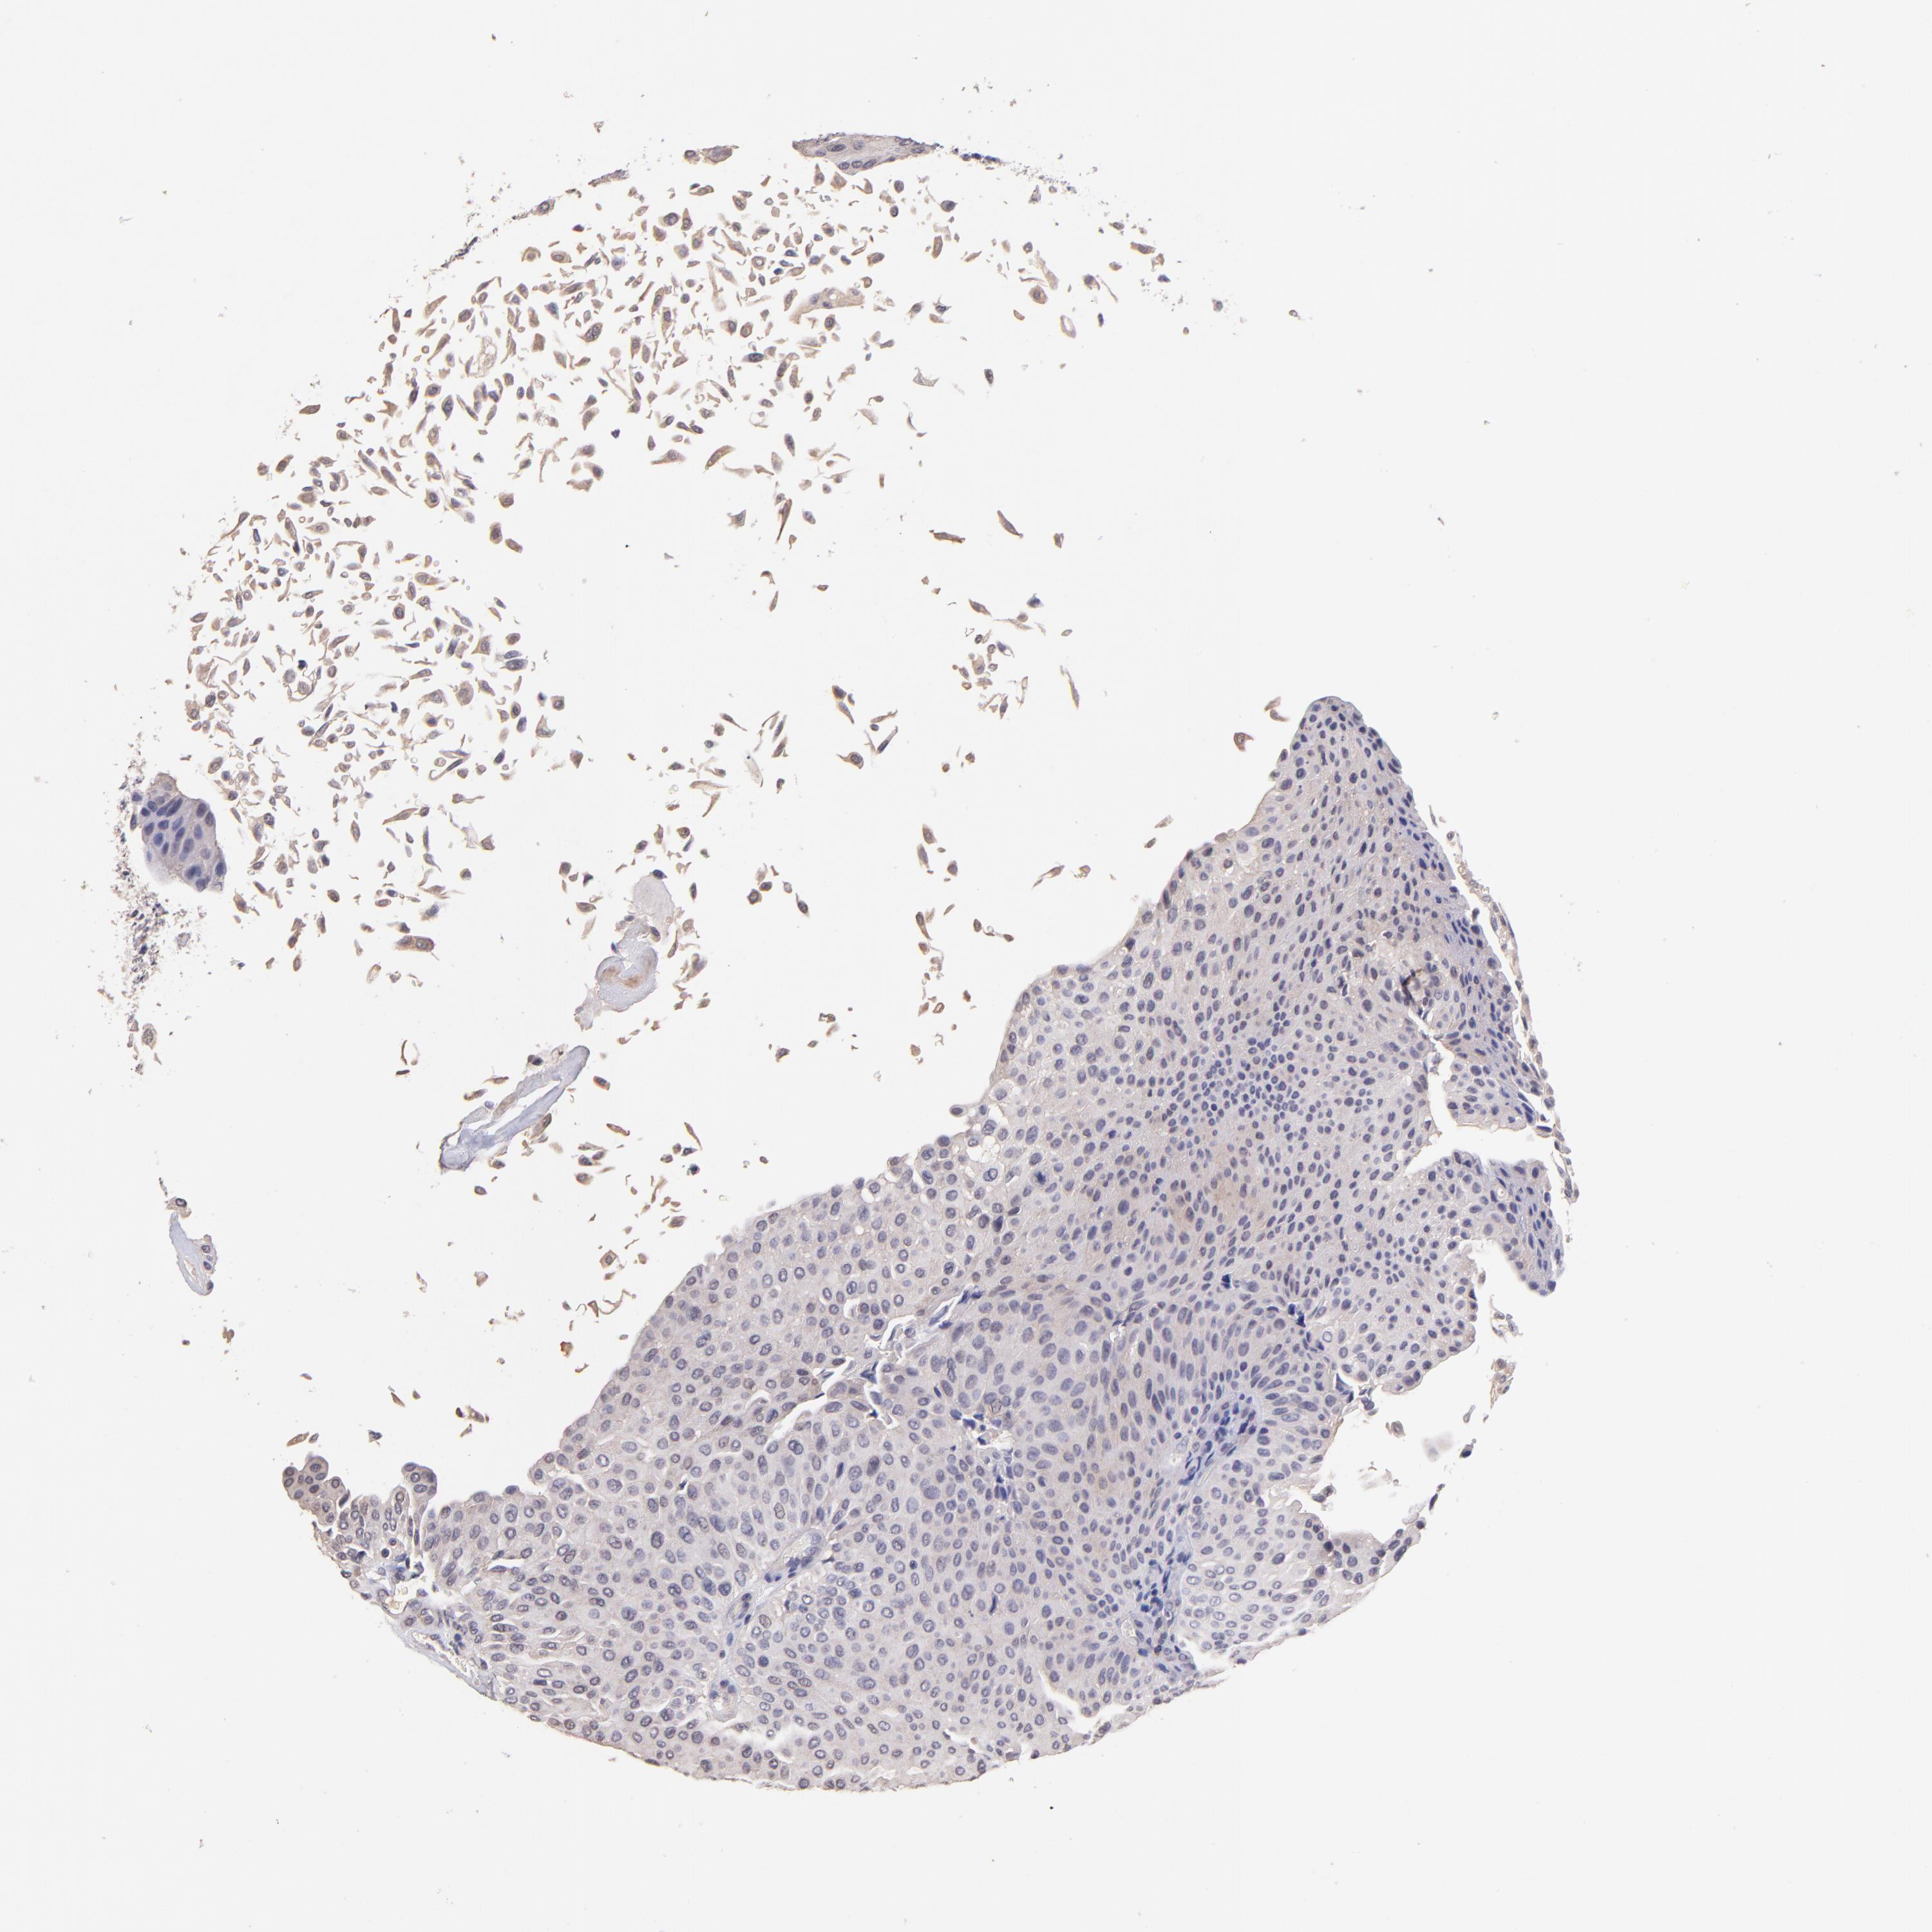

UROTHELIAL CANCER - Protein expressioni

A mouse-over function shows sample information and annotation data. Click on an image to view it in a full screen mode. Samples can be filtered based on level of antibody staining by selecting one or several of the following categories: high, medium, low and not detected. The assay and annotation is described here.

Antibody stainingi

Antibody staining in the annotated cell types in the current human tissue is reported as not detected, low, medium, or high, based on conventional immunohistochemistry profiling in selected tissues. This score is based on the combination of the staining intensity and fraction of stained cells.

Each image is clickable and will lead to virtual microscopy that enables deeper exploration of all samples and also displays staining intensity scores, fraction scores and subcellular localization as well as patient and tissue information for each sample.

Antibody HPA002633

Antibody HPA046758

Antibody CAB010906

Urothelial carcinoma, High grade

Urothelial carcinoma, Low grade